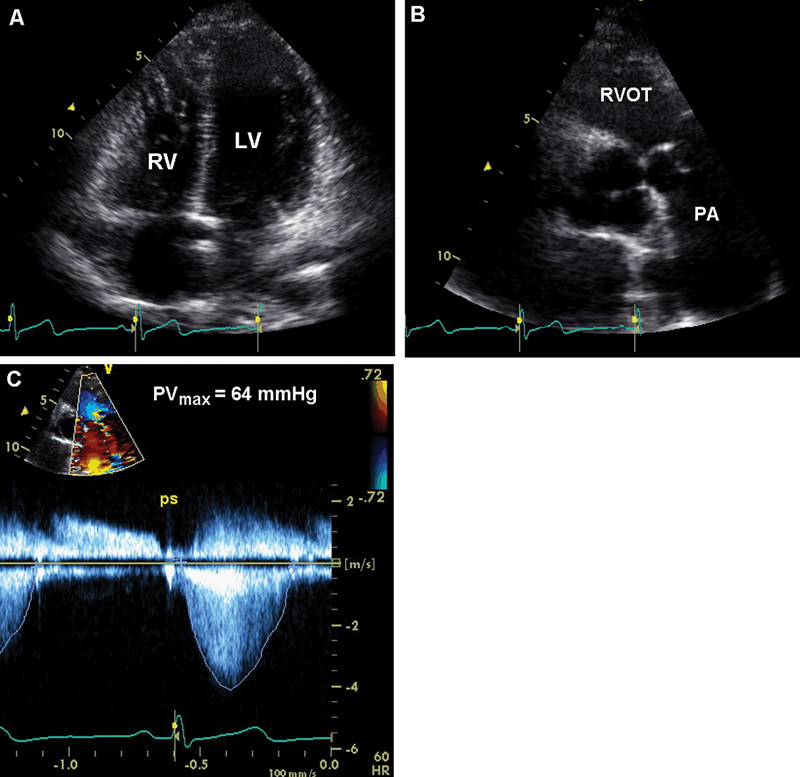

فحوصات تشخيصية لبعض امراض القلب والشرايين التاجية